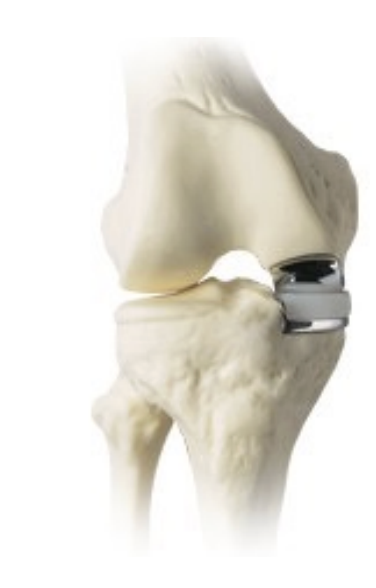

Uniarthroplasty

used for isolated medial

> lateral compartment disease

all ligaments must be intact

<8% of all arthroplasties

good candidates are normal weight, elderly

Patellofemoral replacement